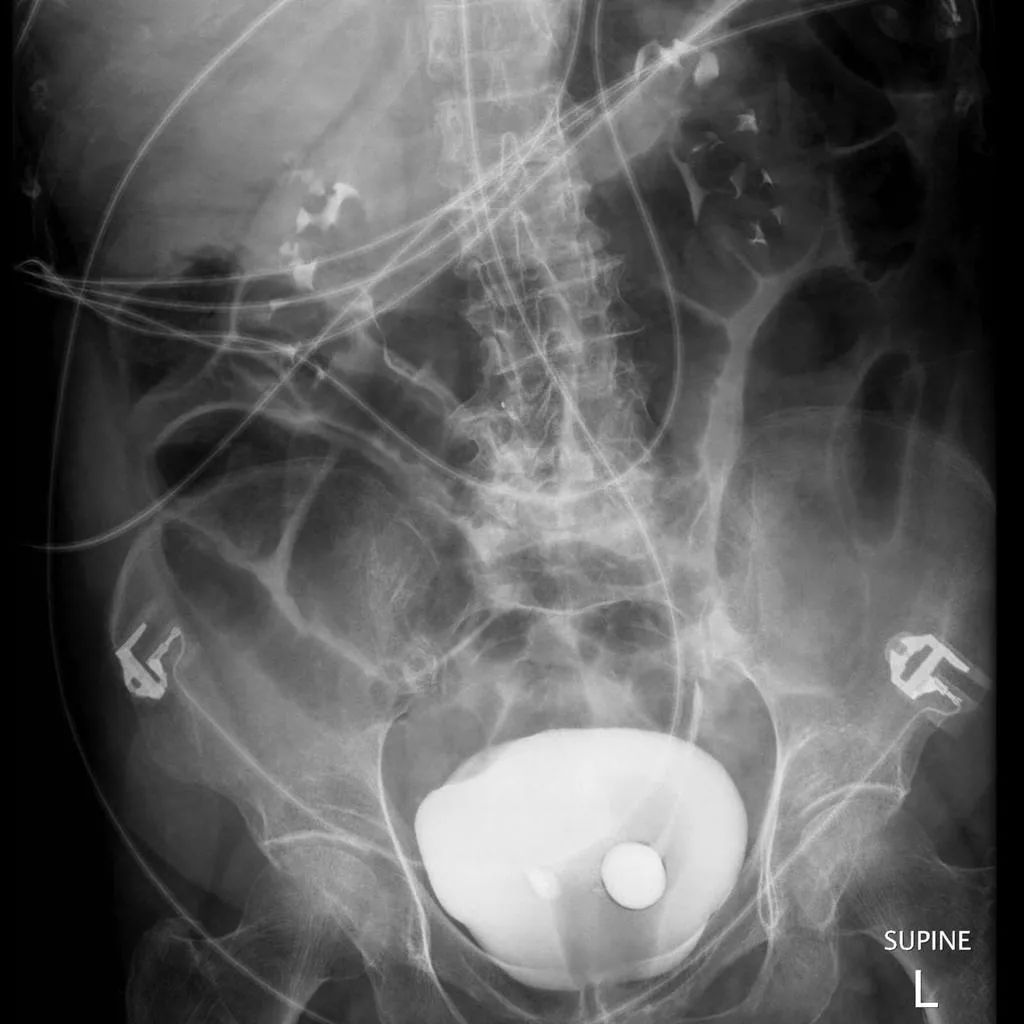

B超显示:左肾积水,左肾盂分离20mm。左输尿管中上段扩张,内径12 mm。可见膀胱结石。

静脉尿路造影:输尿管下端扩张,如眼镜蛇头样,位于膀胱内,其周围为线样透亮影环绕,提示输尿管囊肿。

诊断:左肾积水,左侧输尿管中上段扩张,输尿管囊肿。

输尿管囊肿是由于输尿管开口狭窄及输尿管膀胱壁段肌层发育缺陷,输尿管末端膨大而形成囊肿突入膀胱。女性发病率约为男性的4倍。有2种类型:原位型,囊肿侧的输尿管口位置正常或接近正常,梗阻较轻,所属肾脏损害并不严重,囊肿基本上位于膀胱内。异位型多见,多伴患侧重复肾和双输尿管,囊肿较大,女性用力排尿时,可见部分囊肿从尿道口脱垂,多伴患侧肾功能障碍严重。本例患儿由于囊肿膨入膀胱内,故B超检查认为膀胱内占位,其内有结石,故B超及X线检查均认为膀胱结石。